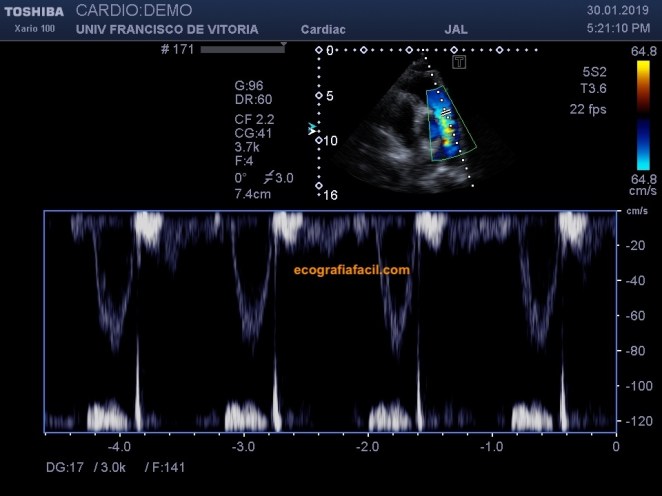

Me gustaría enseñarte como es un pene sano y vigoroso y como es un pene con afectación de la enfermedad de Peyronie, con las dos imágenes de arriba creo que lo vas a entender muy bien, así que una vez explicado como podría ser la anatomía macro morfológica de una pene erecto sano y un pene afectado, nos adentramos en la descripción ecografía de los hallazgos de la enfermedad, vamos.